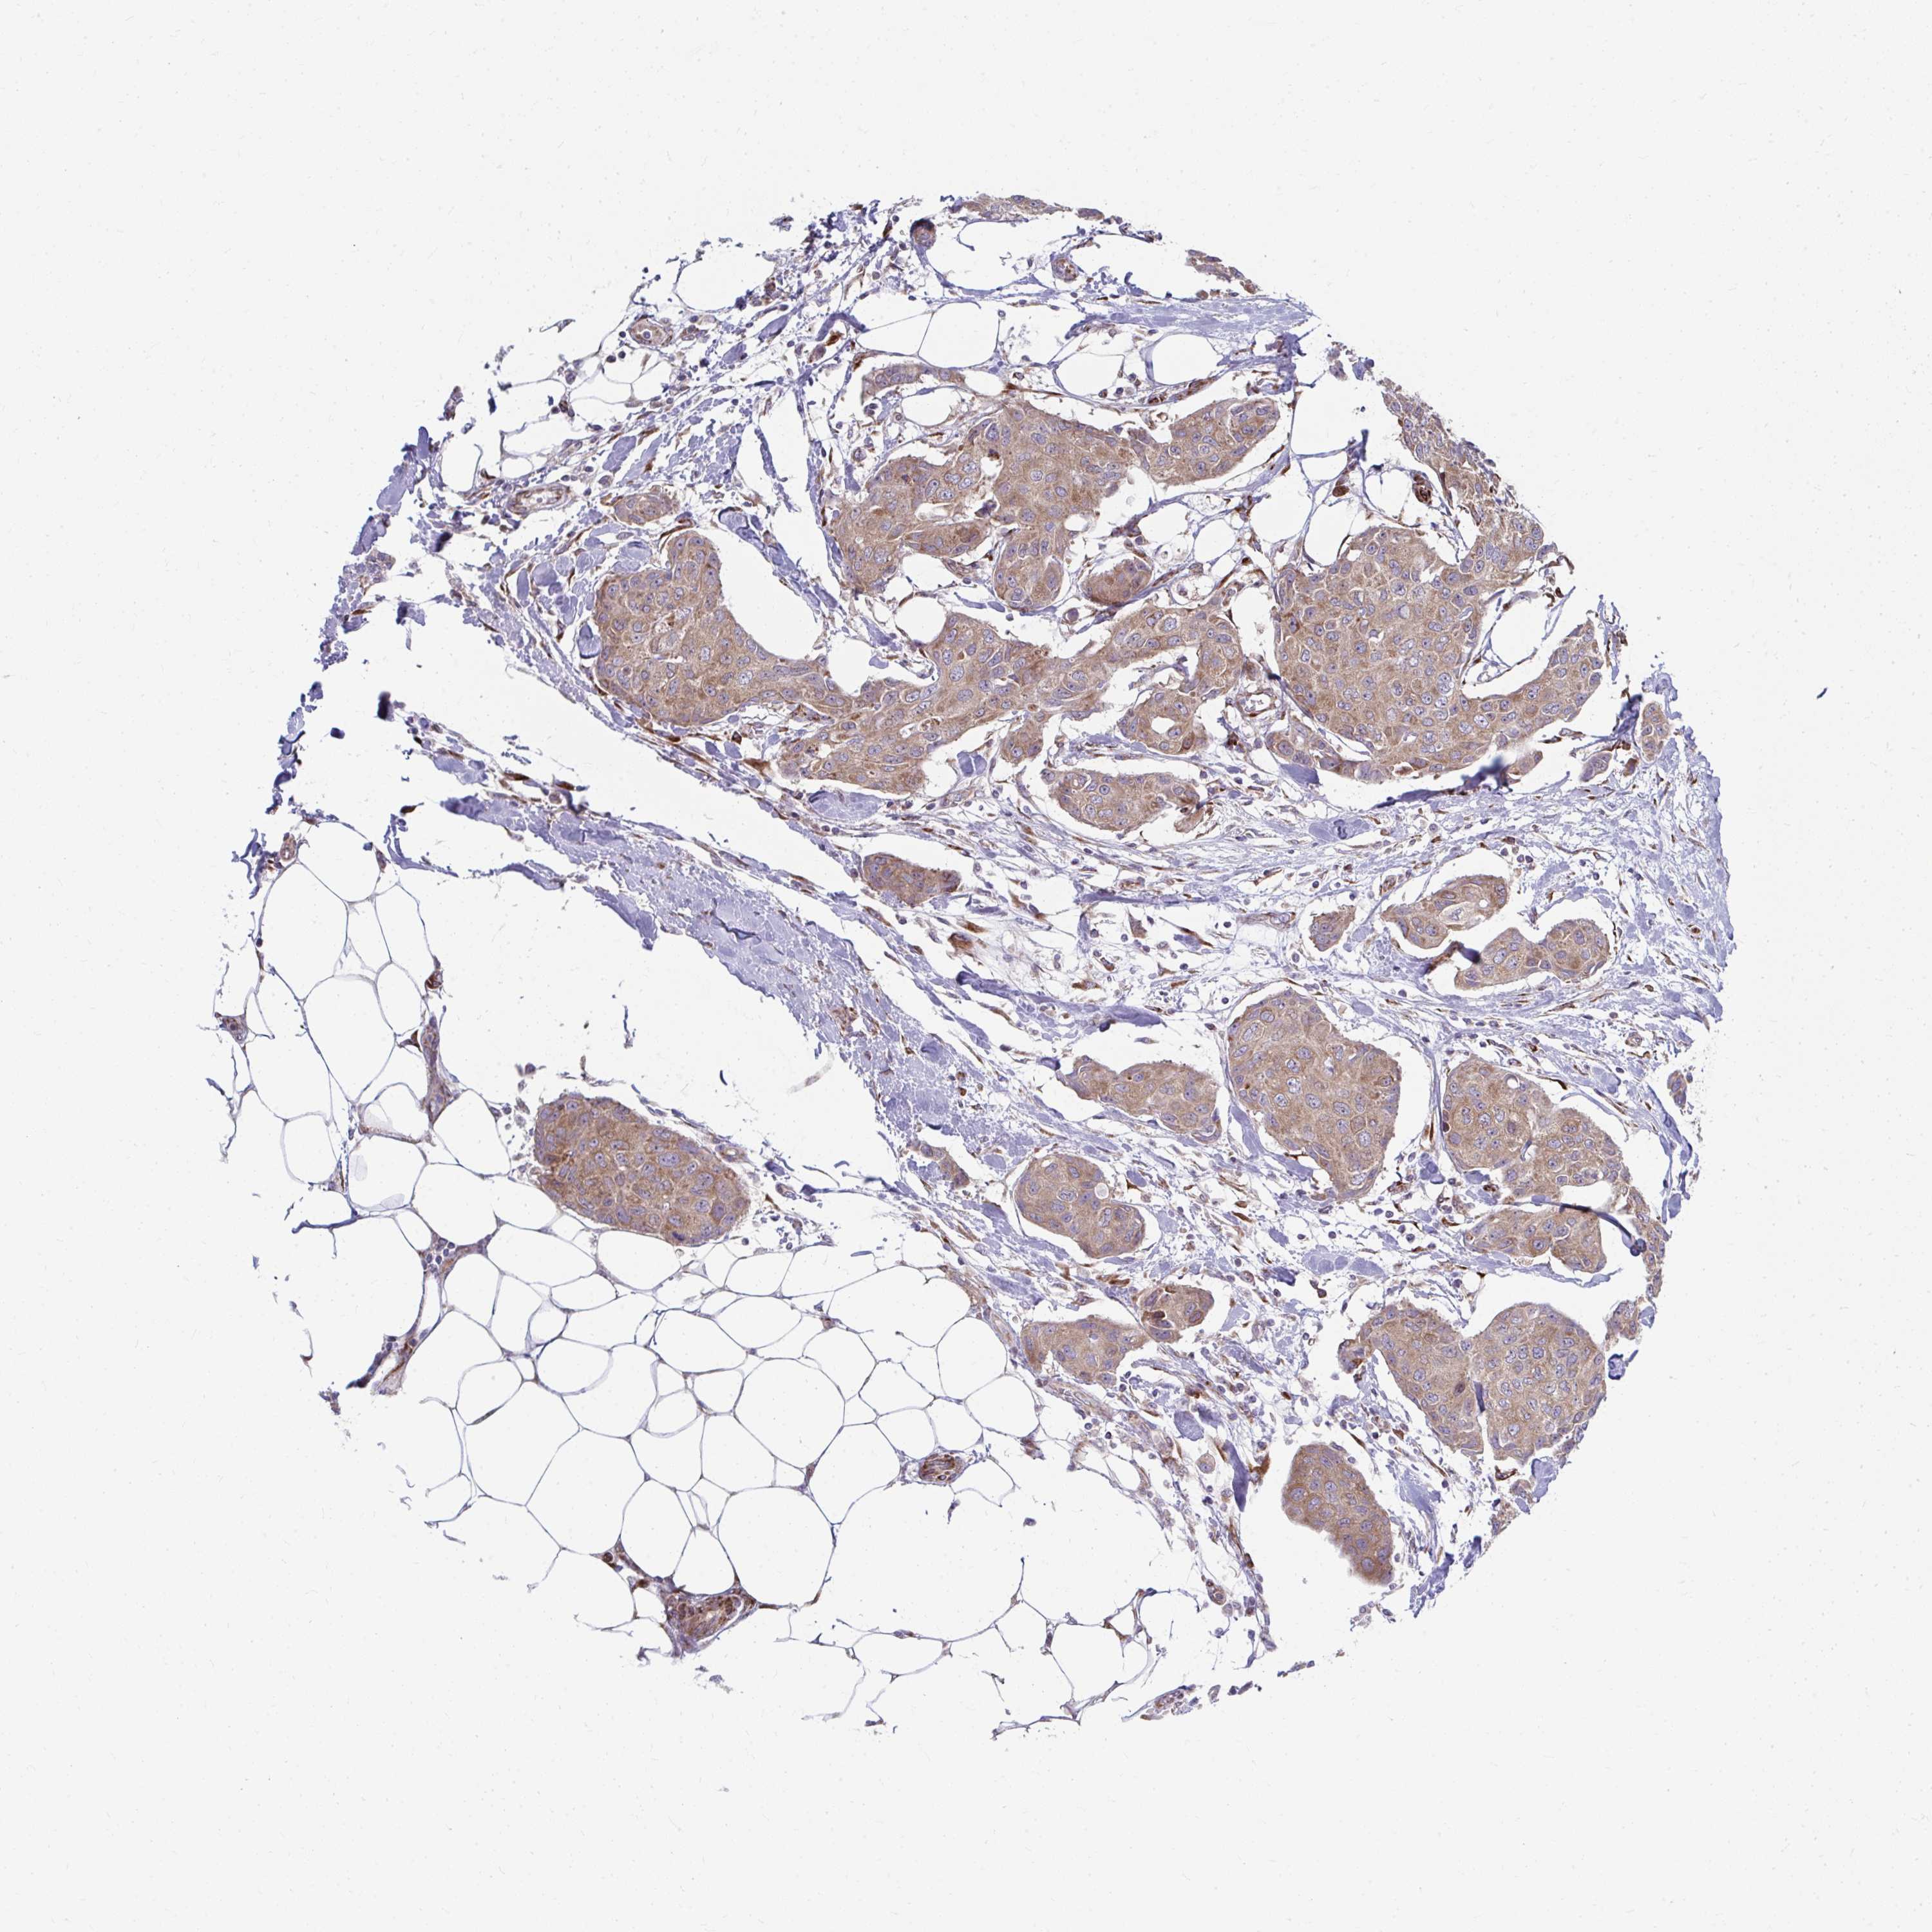

CANCER BREAST CANCER Show tissue menu

BRCA TCGA BRCA VALIDATION PROTEIN EXPRESSION